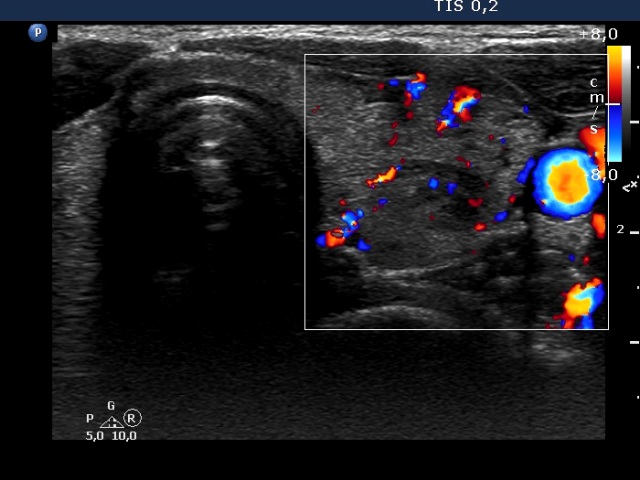

Right lobe, longitudinal scan

Left lobe, transverse scan, color Doppler mode. The vascularization is a bit increased.